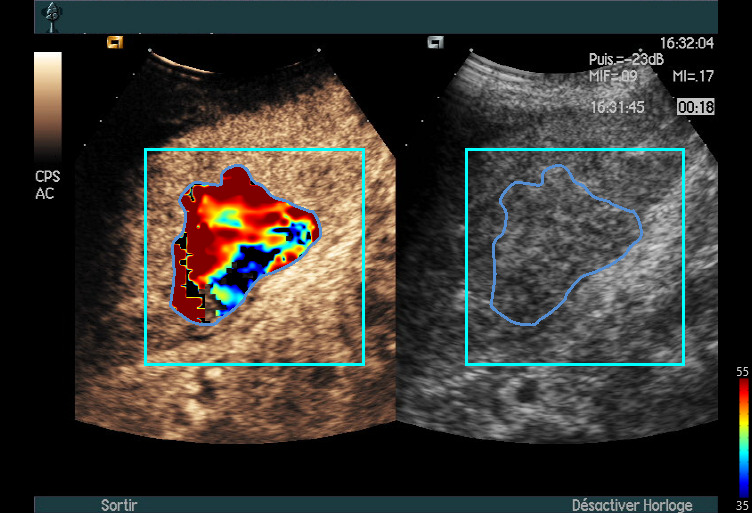

Tissue Normalization

• To highlight differences in contrast enhancement patterns in different regions of interest of the analysed tissue.

Provide tools to summarize the specificities of the difference signals signatures into a single, easy-to-read color-coded image.